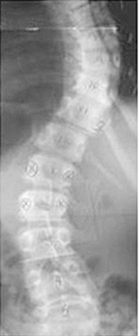

패널의 수치를 통한 척추마디의 실사이즈 측정가능

SOCLIO의 Lead Line이 척추의 휨 정도를 쉽게 판단할 수 있도록 하며 Radiography에 도출될 수 있도록 Lead Line이 폭넓게 분포되어 있습니다. 또한 2, 3장으로 분할 획득한 영상을 쉽게 조합 가능하며 정밀한 하나의 Spine 이미지를 얻을수 있습니다.